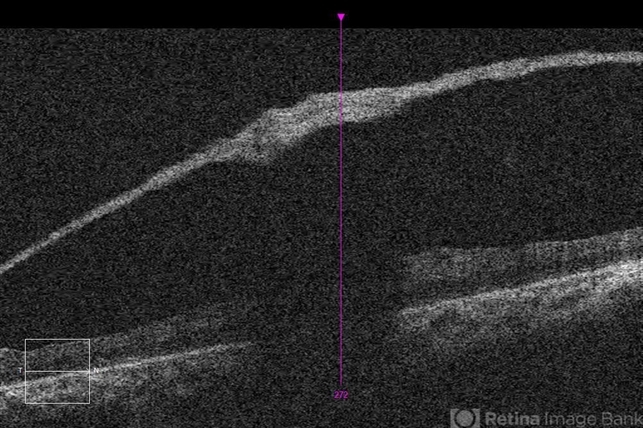

- retinoschisis, retinal hole

- Imaging device

Optical coherence tomography system

Zeiss Cirrus 5000 - Description

- 21-year-old male with congenital retinoschisis with bilateral macular involvement and large inner retinal hole OD.